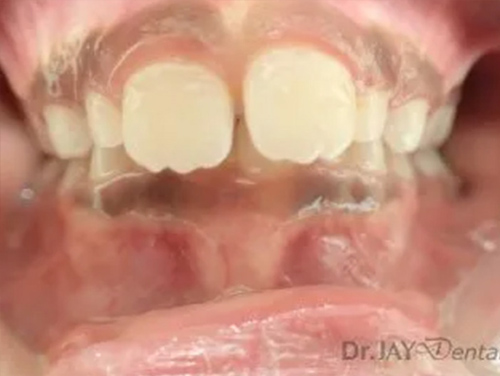

Patient had open bite and severe mouth breathing . At our office , patient went through myofunctional therapy , expansion of upper and lower jaw and aligning of teeth . No extractions needed and orthodontics was focused on airway, correcting habits and giving importance to the holistic health of patient. Patient’s mom extremely happy with the result.

Before

After